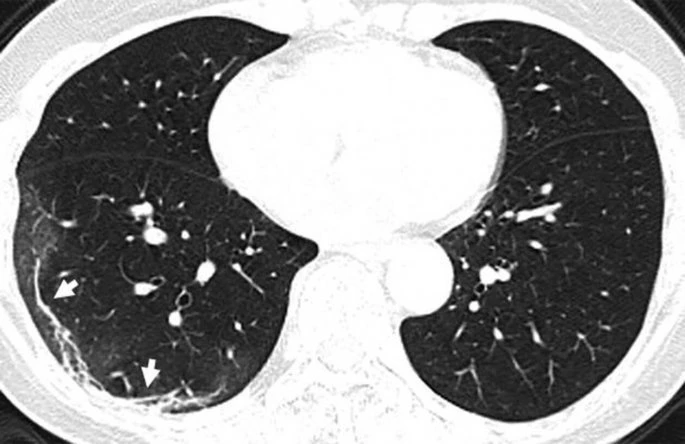

Η πανδημία του κορωνοϊού covid-19 συνεχίζει να καλπάζει σε όλο τον πλανήτη, με τους γιατρούς να παρακολουθούν την έξαρσή του. Περισσότεροι από 4.000 άνθρωποι έχουν χάσει τις ζωές τους από τις επιπλοκές του ιού, ο οποίος προκαλεί σοβαρό πρόβλημα στους πνεύμονες των ασθενών. Στην δημοσιότητα δόθηκαν από την Ραδιολογική Κοινότητα της Βορείου Αμερικής ακτινογραφία πνευμόνων ασθενών, οι οποίοι είχαν προσβληθεί από τον κορωνοϊό, οι οποίες προκαλούν ανατριχίλα.

Οι ασθενείς που έχουν νοσήσει μέχρι στιγμής έχουν περιγράψει την εμπειρία τους ως μια «τρομακτική προσπάθεια για να αναπνεύσουν». Στις ακτινογραφίες διακρίνονται κάποια άσπρα σημάδια, χαμηλά στους πνεύμονες. Περιγράφονται ως υγρό στις κυψέλες του πνεύμονα. Να σημειώσουμε πως οι ακτινογραφίες αυτές που δόθηκαν στην δημοσιότητα είναι από ασθενείς από την Κίνα που νόσησαν με επιπλοκές, οπότε δεν έχουν καμία σχέση με το αν νοσήσει κάποιος ο οποίος δεν αντιμετωπίζει προβλήματα υγείας.